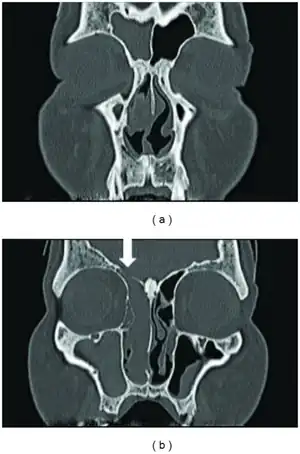

| Nasal glioma, seen on T2-weighted coronal MRI | |

Nasal glioma is a rare benign congenital lesion, usually a firm, incompressible, reddish-blue to purple lesion occurring on the nasal bridge or midline near the root.[1][2]: 622